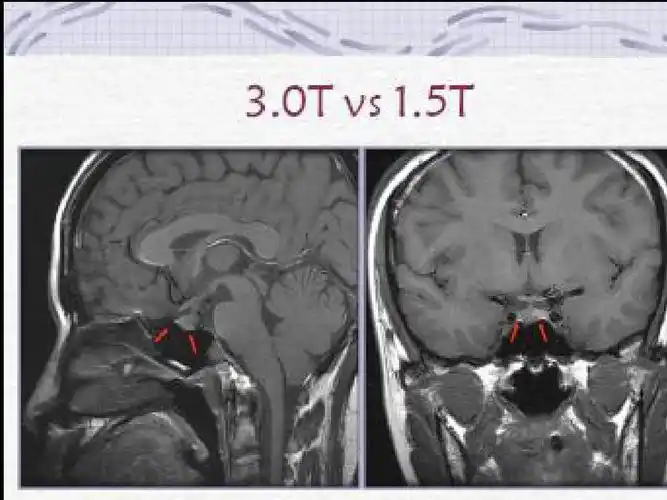

垂体病变的mri诊断ppt